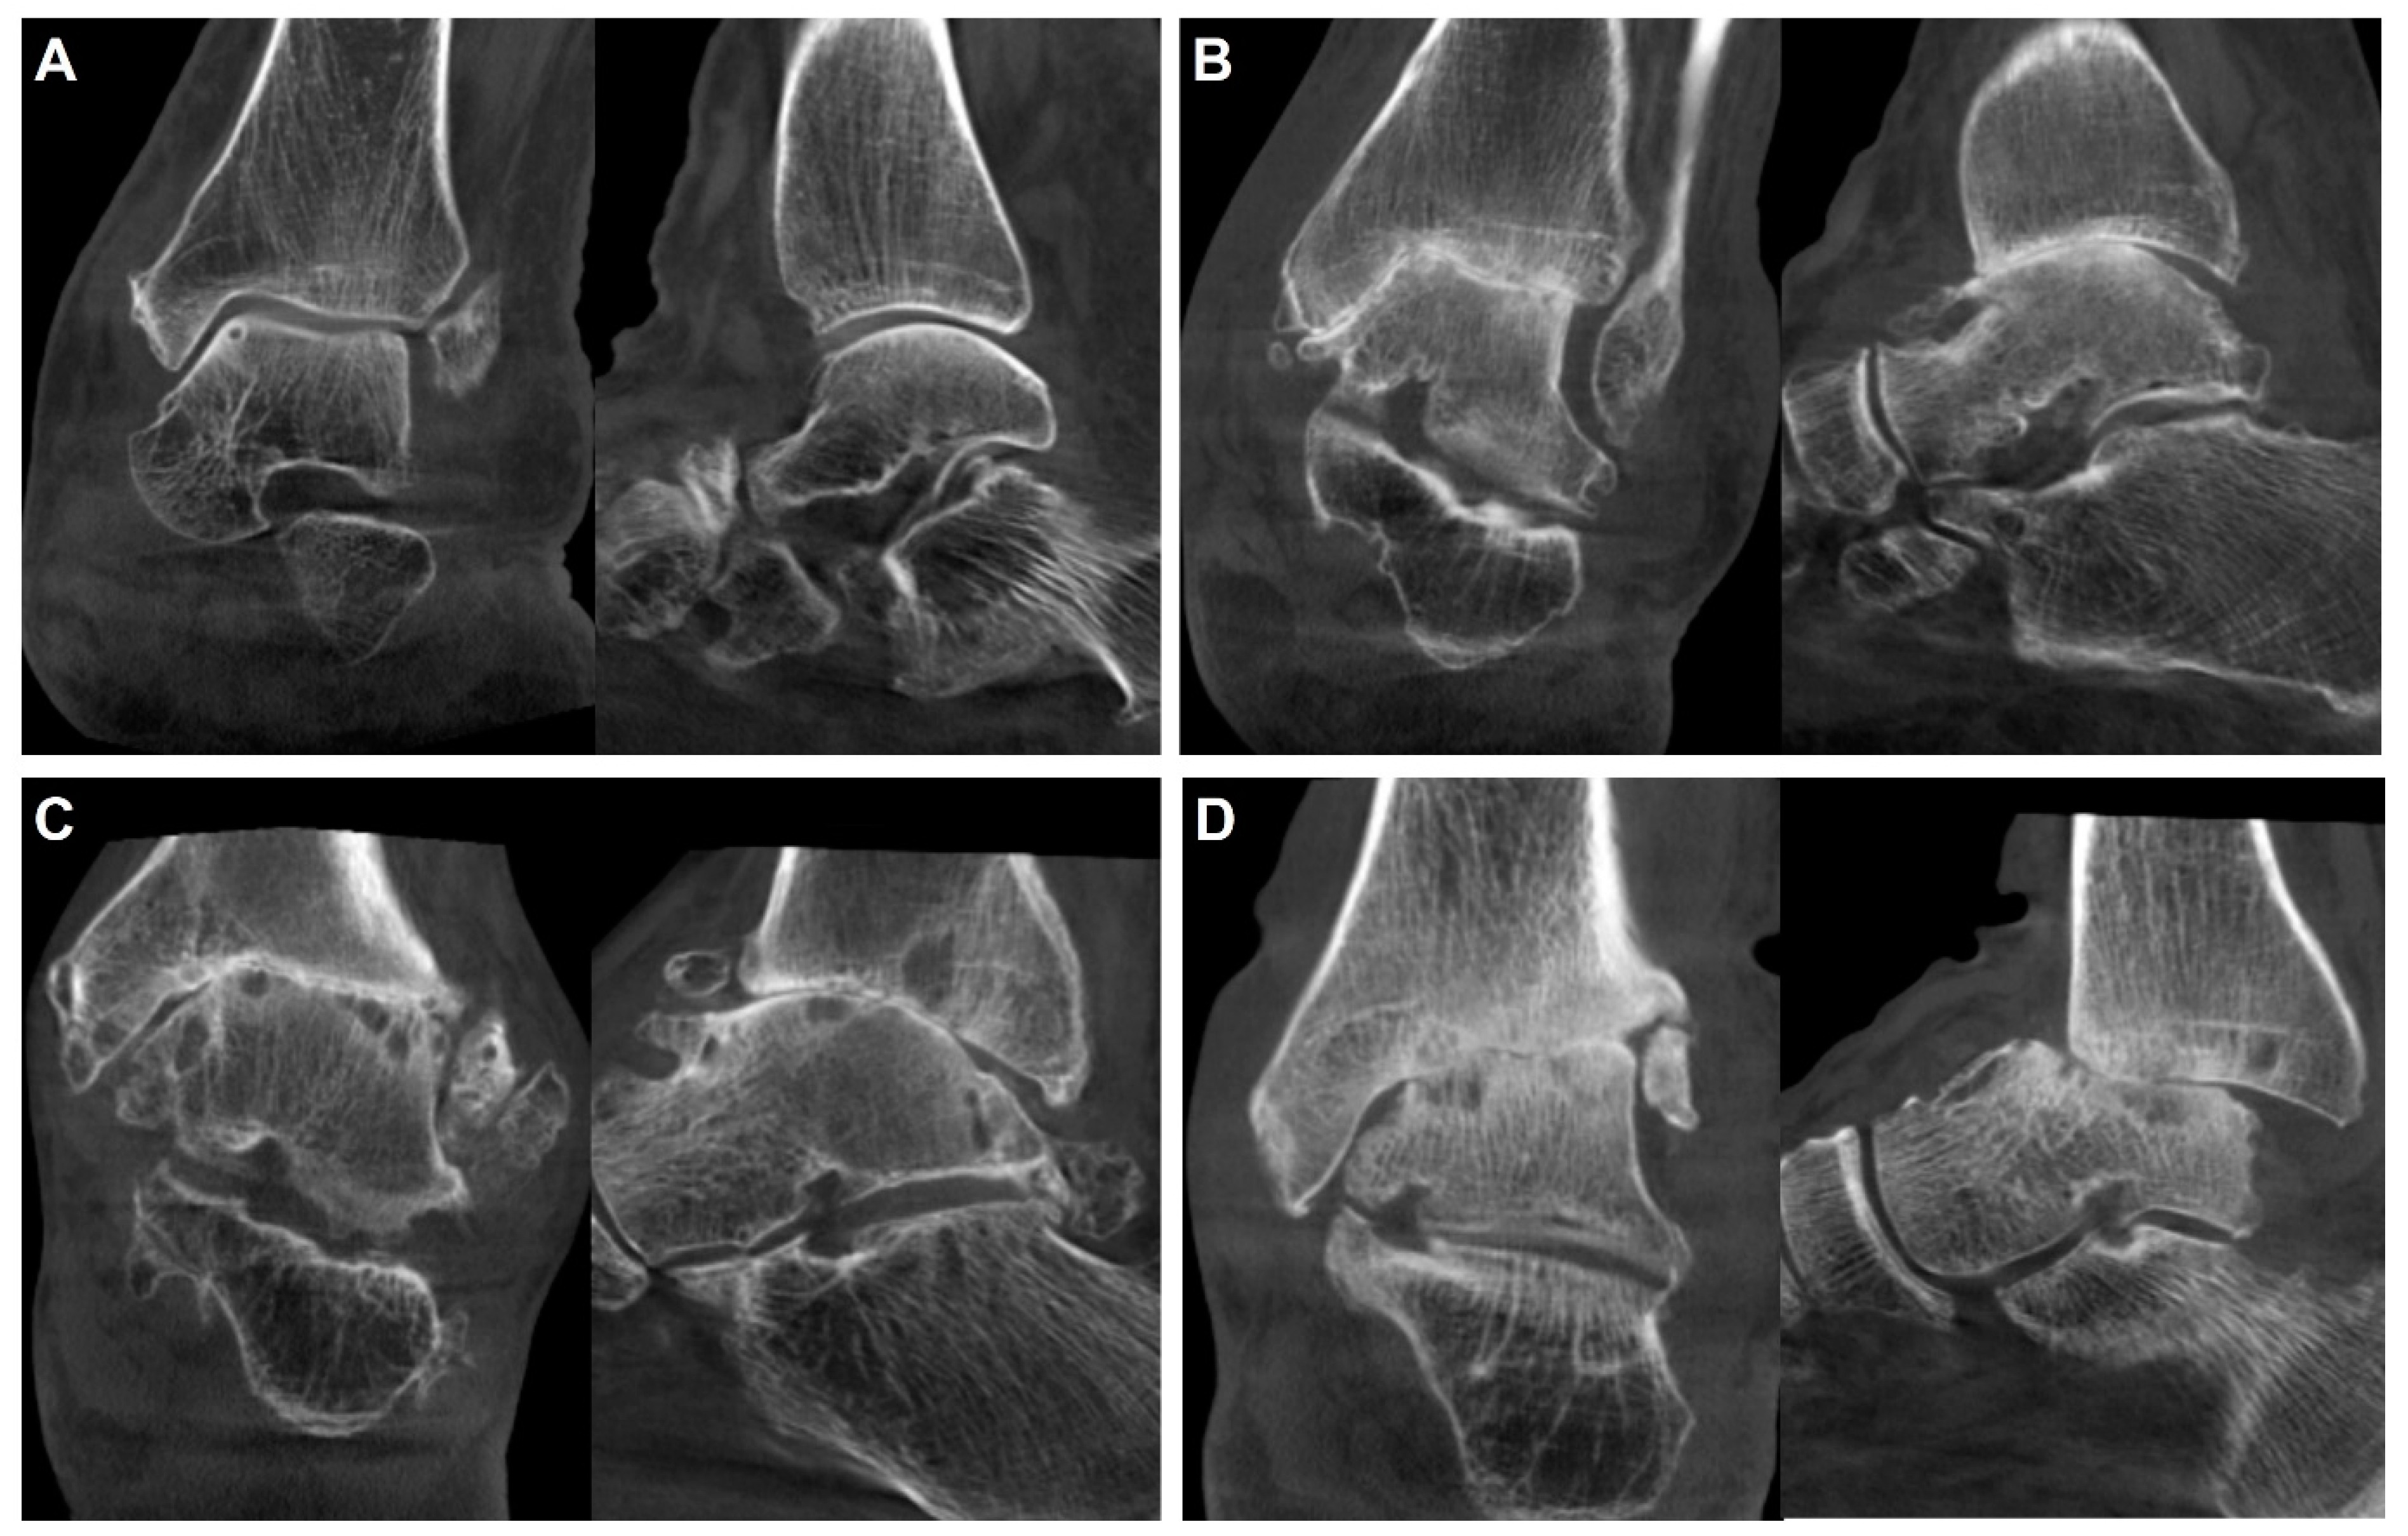

- Kang, H.W.; Kim, D.Y.; Park, G.Y.; Lee, D.O.; Lee, D.Y. Coronal plane Calcaneal-Talar Orientation in Varus Ankle Osteoarthritis. Foot Ankle Int. 2022, 43, 928–936. [Google Scholar] [CrossRef]